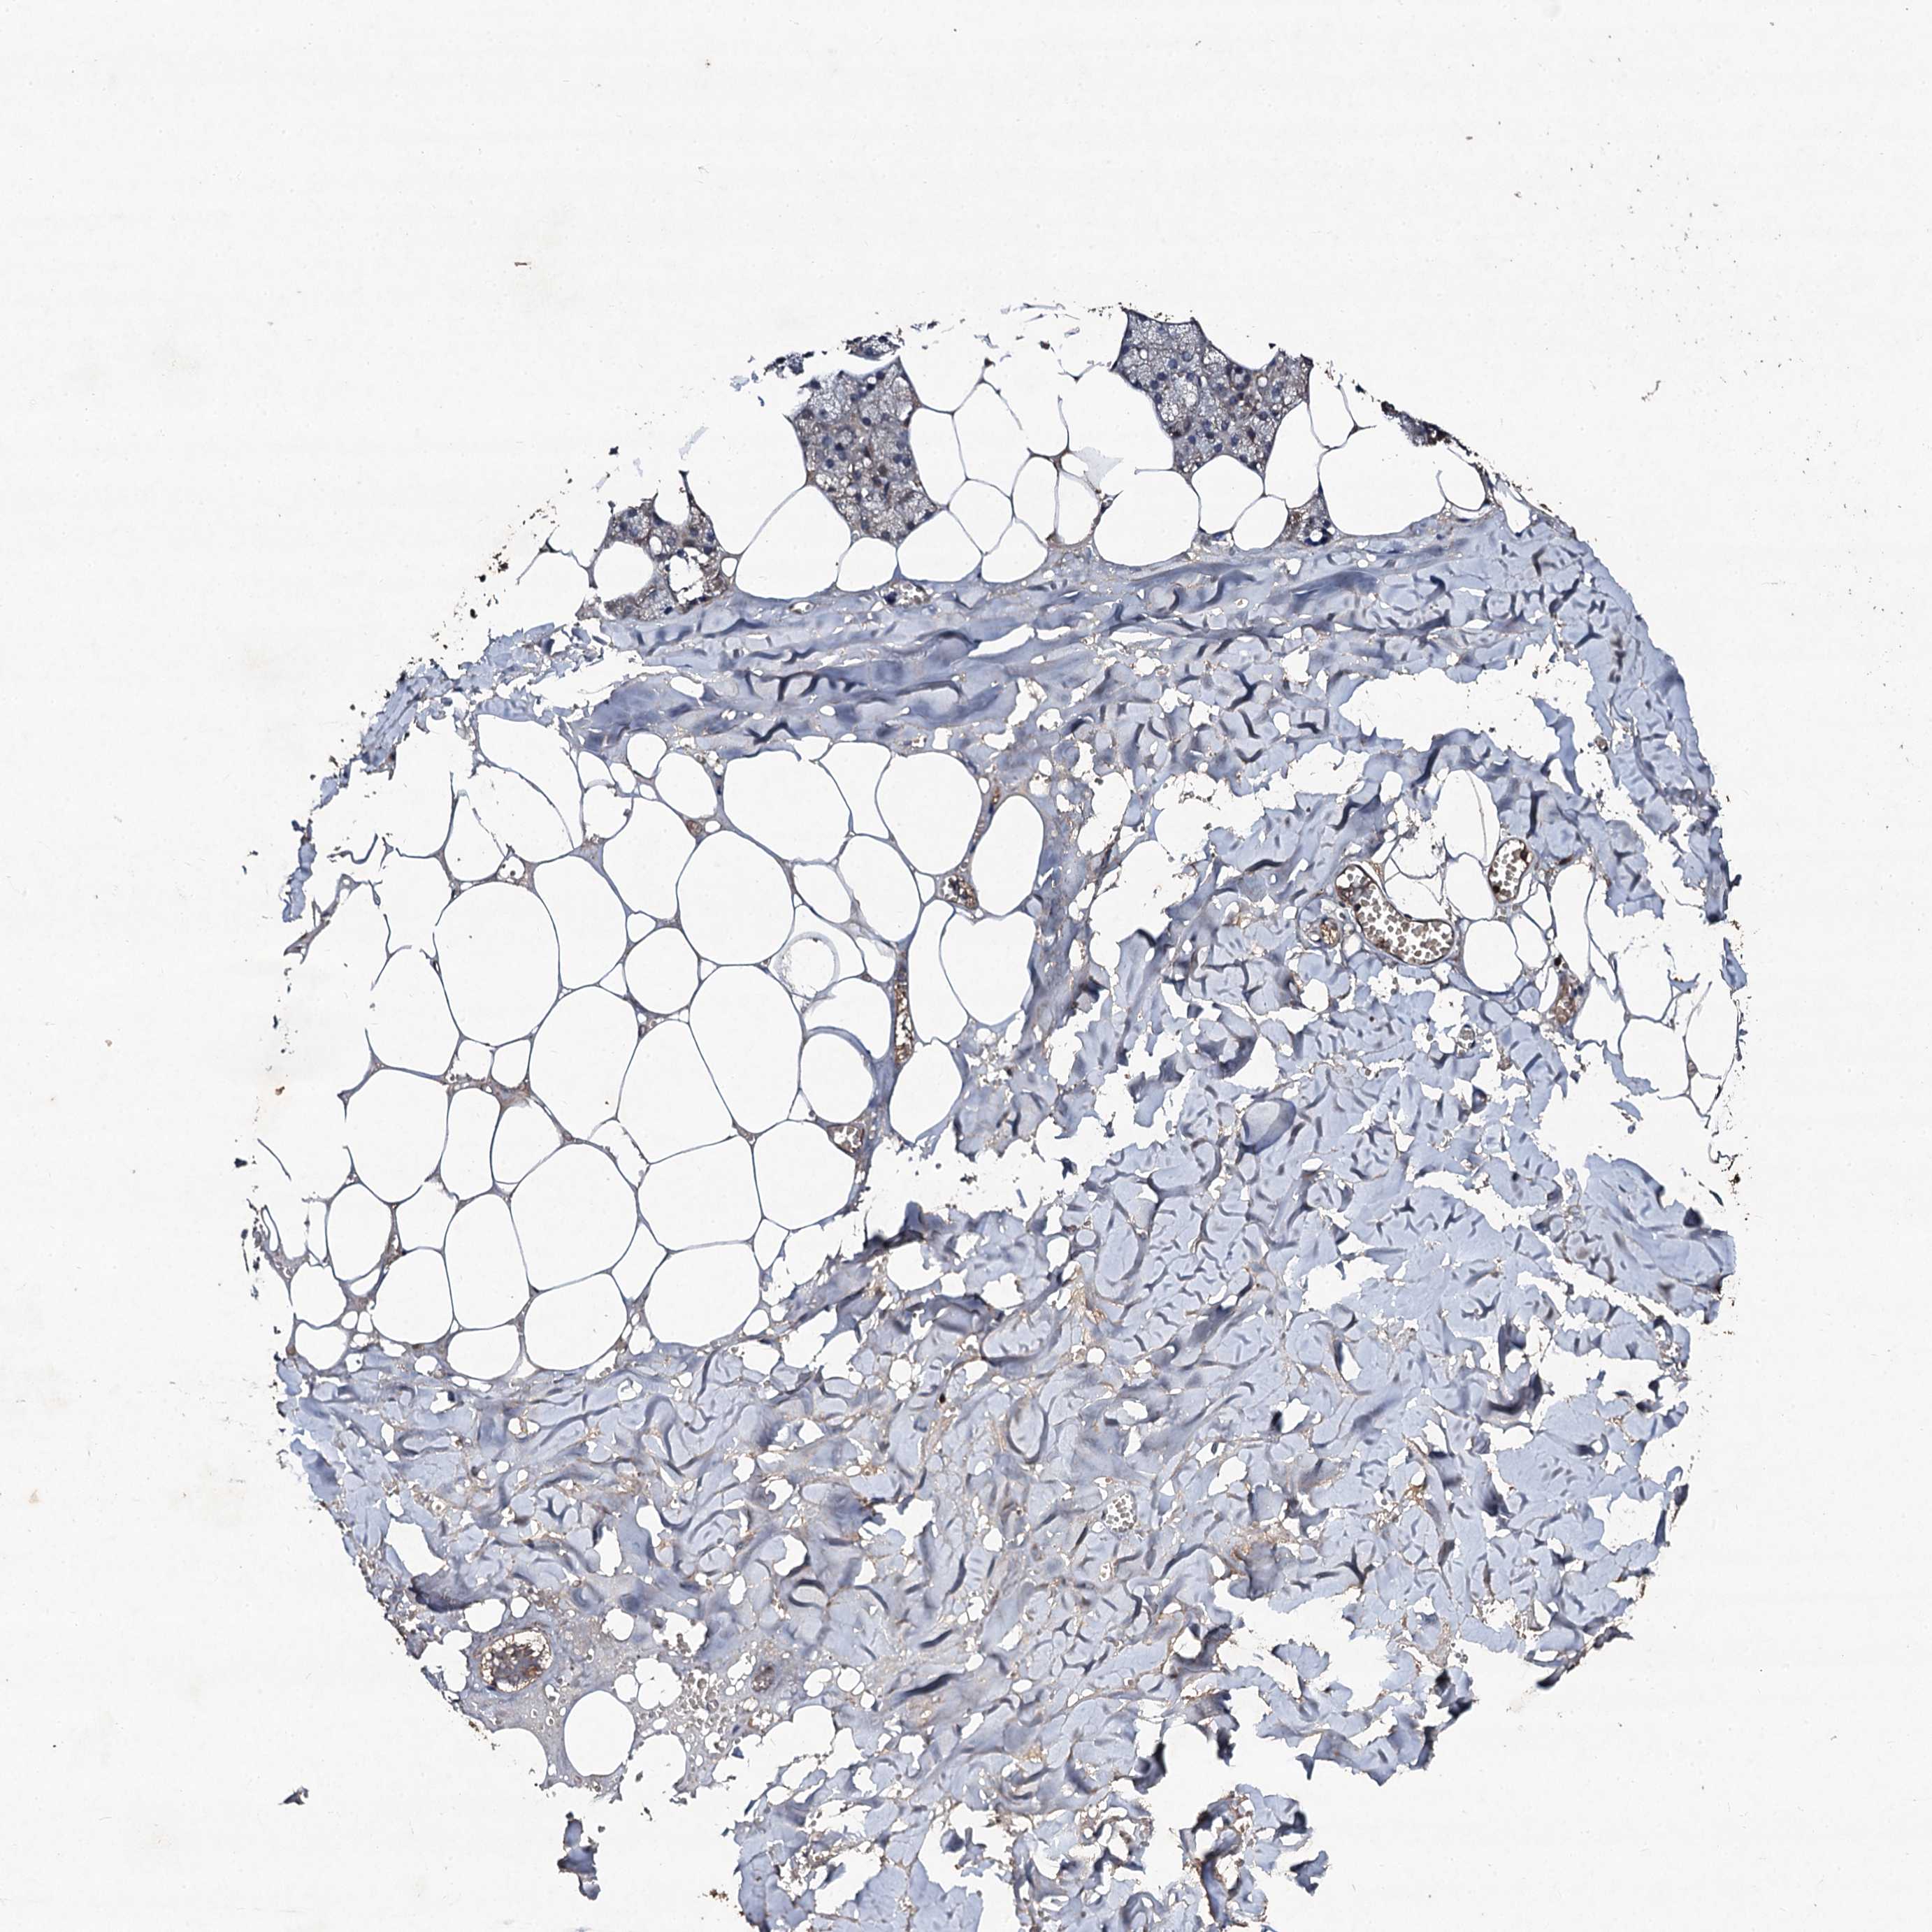

SALIVARY GLAND - HPA RNA-seqi

The RNA-seq details section shows detailed information about the individual samples used for the transcript profiling and results of the RNA-seq analysis.

Information about each individual sample is listed below, including gender, age, a tissue section image and estimated fractions of cell types. nTPM (normalized transcripts per million) values give a quantification of the gene abundance which is comparable between different genes and samples.

overview

Male, age 60

Salivary gland sample 217

nTPM: 0

Cell types%

Glandular cells:

55

Ductal cells:

20

Adipocytes:

5

Endothelial cells:

Other cell types:

15